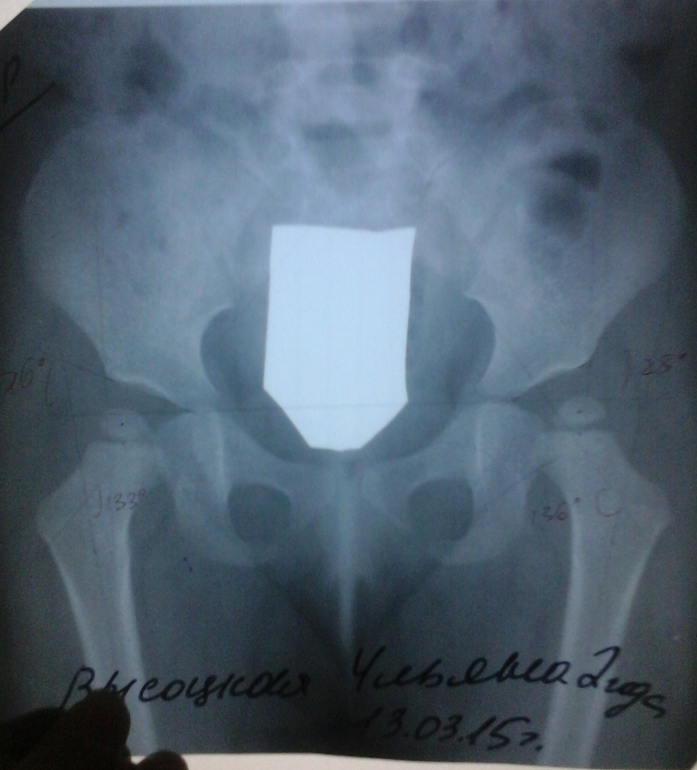

Доброе утро! Отписываюсь о консультации с Волошиным С.Ю. Вот наше лечение с продолжением http://www.babyblog.ru/community/post/Displaziya/1876003, http://www.babyblog.ru/community/post/Displaziya/3216991. С.Ю. осмотрел, сказал сразу, что проблемы есть, снимки у нас были сделаны с неправильной укладкой, шину с нас сняли рано, была "явная дисплазия", поэтому сейчас "огромные углы". Прописывали нам сейчас электрофорез с тиосульфатом натрия, он нам совершенно был не нужен... прописал с тренталом через месяц, в середине лета сделать массаж, заниматься плаванием, делать минеральные ванны. В ноябре сделать рентген и выслать ему снимки... Сказал возможно выкарабкаемся...

Дочери сейчас 2 года, наша история лечения здесь http://www.babyblog.ru/community/post/Displaziya/1876003, в 9 месяцев сняли шину и с диагнозом здорова отпустили на 2 месяца, на приеме в 11 мес - здоровы, рентген не требуется, через полтора месяца - здоровы, рентген не требуется и отпускают нас до 2-х лет. Пришли на долгожданный приём, врачу всё нравится, всё замечательно, но сделайте ка контрольный рентген, сделали рентген и о ужас! ДТС с обеих сторон (подвывих сохраняется). Езжайте на консультацию к Волошину С.Ю. - здесь нам уже ни чем помочь не могут(((((((((((((((